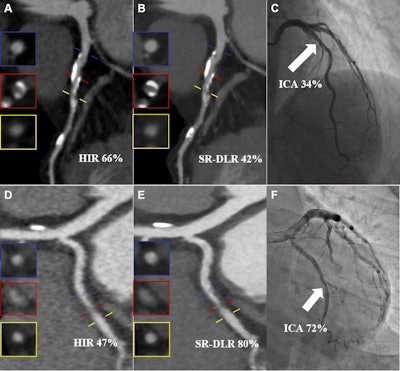

Images from two representative cases. (A-C) Images in an 82-year-old man with a calcified plaque in the proximal segment of the left anterior descending artery. (A, B) Curved planar reconstruction images from CCTA with (A) hybrid iterative reconstruction (HIR) and (B) super-resolution deep learning reconstruction (SR-DLR) show that the measured PDS was 66% for the HIR image and 42% for the SR-DLR image. (C) Quantitative analysis of the invasive coronary angiography (ICA) image (reference standard) revealed a PDS of 34% (arrow). (D-F) Images in a 37-year-old woman with a noncalcified plaque in the middle segment of the left circumflex artery. (D, E) Curved planar reconstruction images from CCTA with (D) HIR and (E) SR-DLR show that the measured PDS was 47% for the HIR image and 80% for the SR-DLR image. (F) Quantitative analysis of the ICA image revealed a PDS of 72% (arrow). Blue, red, and yellow lines in A, B, D, and E represent the proximal reference point, stenosed lesion, and distal reference point, respectively, and the insets show the corresponding cross-sectional images.Images from two representative cases. (A-C) Images in an 82-year-old man with a calcified plaque in the proximal segment of the left anterior descending artery. (A, B) Curved planar reconstruction images from CCTA with (A) hybrid iterative reconstruction (HIR) and (B) super-resolution deep learning reconstruction (SR-DLR) show that the measured PDS was 66% for the HIR image and 42% for the SR-DLR image. (C) Quantitative analysis of the invasive coronary angiography (ICA) image (reference standard) revealed a PDS of 34% (arrow). (D-F) Images in a 37-year-old woman with a noncalcified plaque in the middle segment of the left circumflex artery. (D, E) Curved planar reconstruction images from CCTA with (D) HIR and (E) SR-DLR show that the measured PDS was 47% for the HIR image and 80% for the SR-DLR image. (F) Quantitative analysis of the ICA image revealed a PDS of 72% (arrow). Blue, red, and yellow lines in A, B, D, and E represent the proximal reference point, stenosed lesion, and distal reference point, respectively, and the insets show the corresponding cross-sectional images.RSNA